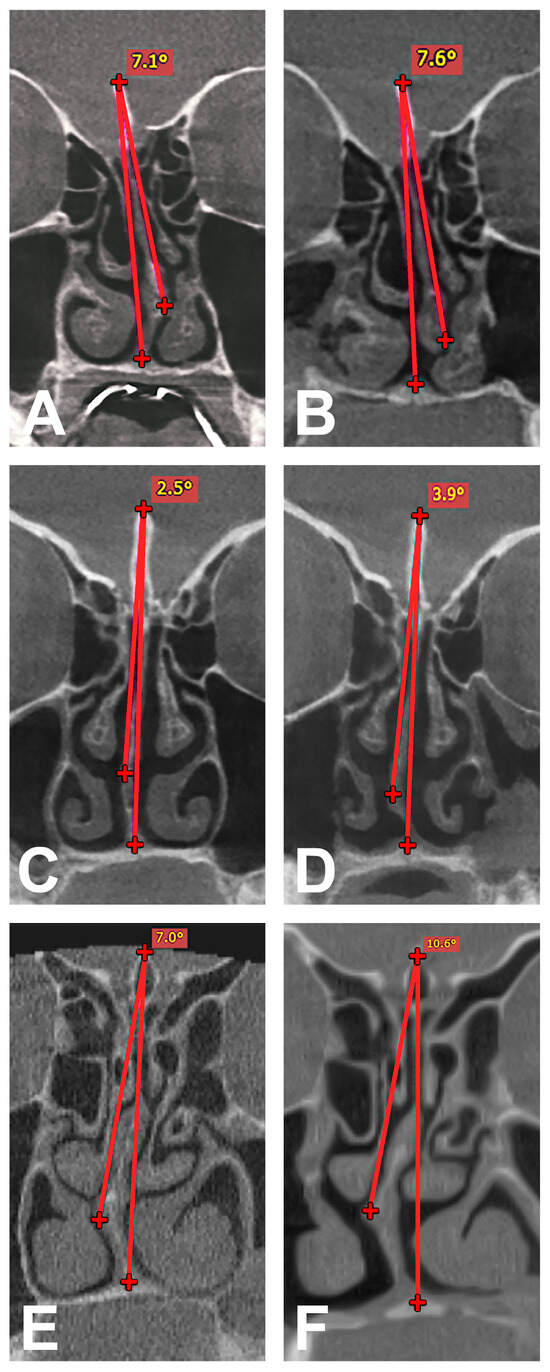

2.3. Radiological Analysis

2.5. Determination of NSD